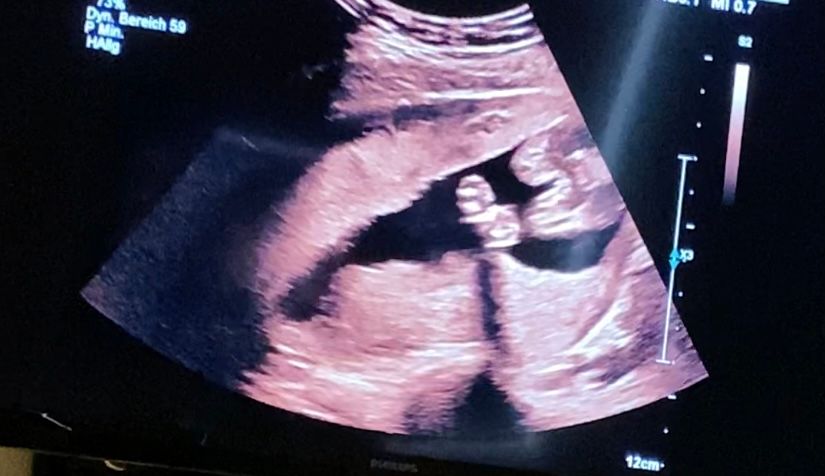

УЗИ, КТГ, доплер18 недель .

Вот на первой фотке вижу пирожок,а на второй бугорок 🤷♀️ Это обе фотки между ножек.

Это 100% девочка. Было подобное фото второе как у вас на вашем же сроке. Врач неопытная тоже озадачилась. Но это девочка

Без сомнений девочка. У сына в 17 недель было видно все очень хорошо. Не спутать с девочкой 😂Поздравляю!!!